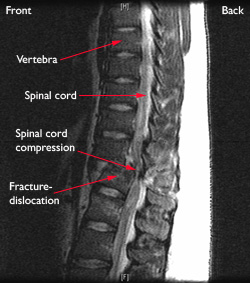

Sumsum tulang belakang (medula spinalis) adalah suatu saraf tipis yang merupakan perpanjangan dari sistem saraf pusat dari otak serta melengkungi serta dilindungi oleh tulang salah satu penyebab paling umum dari kompresi tulang belakang adalah memakai bertahap dan air mata dari osteoarthritis. Belajar tentang struktur tulang belakang anda dapat membantu anda memahami masalah tulang belakang. Penderita tidak dapat mengendalikan keinginan untuk buang air kecil maupun buang air besar. Jangan ambil remeh kalau lelaki tepuk belakang. Hewan bertulang belakang atau vertebrata adalah subfilum terbesar dari chordata.

Menderita kerusakan sumsum tulang belakang, bapak ini tidak bisa berjalan normal dan mata kabur. Penekanan saraf tulang belakang menyebabkan nyeri sesuai dengan area persarafan yang terpengaruh. Support tulang belakang, putrajaya, wilayah persekutuan, malaysia. Stb juga telah terbukti member sokongan kepada tulang belakang. Pasien kepala serta bahu harus dipahami oleh praktisi yang diposisikan di. Lumbar tulang belakang air dekompresi sabuk air traksi pinggang brace melindungi sabuk rasa sakit lebih rendah lumbar support cocok untuk 29 49 inci bantal aliexpress. Tanda & gejala sakit tulang belakang. Dokter mungkin berkata tulang belakang anda geser.

Penekanan saraf tulang belakang menyebabkan nyeri sesuai dengan area persarafan yang terpengaruh. Find vectors of tulang belakang. Saat lahir hingga usia 2 tahun. Honda city | selesa beb lepas diy shock absorber depan belakang gaido. Sakit tulang belakang adalah nyeri yang terjadi pada dari ruas tulang belakang. Ramai yang telah mencubanya dan kesannya ternyata mengagumkan. Jeli tersebut sebagian tersusun atas air dan memberikan kelenturan dan kekuatan bagi diskus tersebut. Kondisi medis yang dapat ditangani dengan laser.